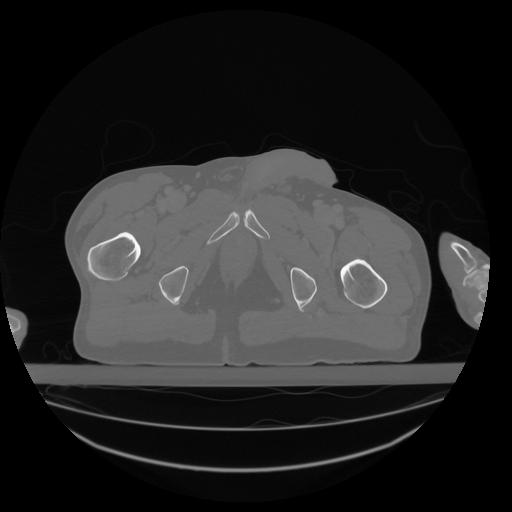

34 CUERPO,CE,Vol,1.0,CUERPO,,